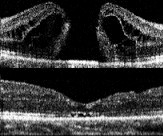

Tomografia de retina pré e pós a cirurgia, com recuperação da anatomia normal da retina.